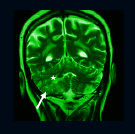

Radiología, física médica y radioprotección:

Verónica Gigirey, Martín Rodríguez Parodi, Enrique Cuña, Diego González, Margarita García Fontes, Liliana Servente